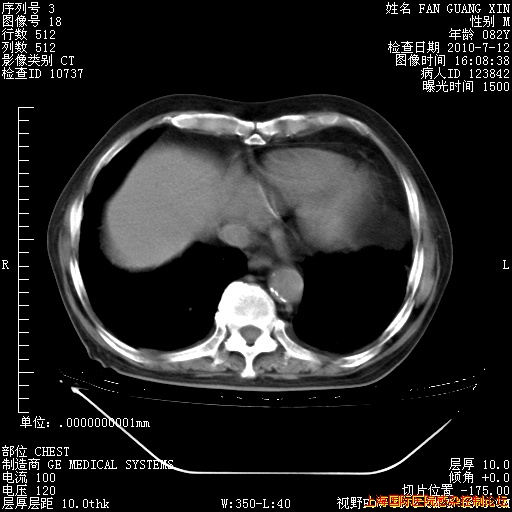

今天CT

整整相隔30天的肺部CT好像有所好转啊。甲强龙减量第3天,需要观察体温。

海管,自昨日你和我通完话后,不知您岳父消化道症状有无缓解?体温怎样?阅读7.12日胸部ct,个人认为目前激素治疗是有效的,甲强龙减量是适宜的。因在抗痨治疗,需密切观察肝功、肾功能和血常规。不过,老年、长期住院和大量使用激素,很担心菌群失调发生